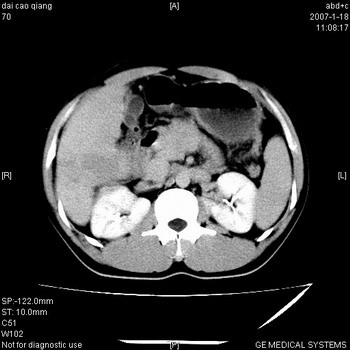

符合巨块型肝癌表现:

1、平扫低密度,增强后表现为快进快出。

2、动脉期可见迂曲的动脉供血血管

3、并可见门静脉右支癌栓形成

4、可见假包膜

5、腹主动脉旁结节影,考虑肿大淋巴结。

肝右叶巨大不均匀低密度肿块,前缘有假包膜,增强明显的呈快进快出表现,门脉右支有癌栓,病人虽然年轻但还是首先考虑肝右叶巨块形肝癌,病人血象高只能说有合并感染。不支持肝脓肿。